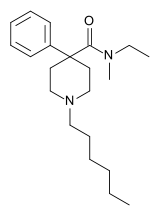

The first fully synthetic opioid was meperidine (later demerol), found serendipitously by German chemist Otto Eisleb (or Eislib) at IG Farben in 1932.[228] Meperidine was the first opiate to have a structure unrelated to morphine, but with opiate-like properties.[199] Its analgesic effects were discovered by Otto Schaumann in 1939.[228] Gustav Ehrhart and Max Bockmühl, also at IG Farben, built on the work of Eisleb and Schaumann. They developed "Hoechst 10820" (later methadone) around 1937.[230] In 1959 the Belgian physician Paul Janssen developed fentanyl, a synthetic drug with 30 to 50 times the potency of heroin.[211][231] Nearly 150 synthetic opioids are now known.[228]

Phenylpiperidines

- Pethidine (meperidine)